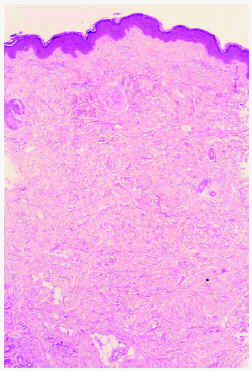

Se practicó una biopsia cutánea de una de las lesiones del paciente (fig. 5).

Fig. 5.--Colágeno maduro y compactado en dermis sin alteraciones inflamatorias. (Hematoxilina-eosina, x40.)

En el examen histopatológico se observa una epidermis normal, con una acumulación en la dermis de colágeno maduro y compactado, con ausencia de cambios inflamatorios, lo cual es compatible con nevos del tejido conjuntivo.